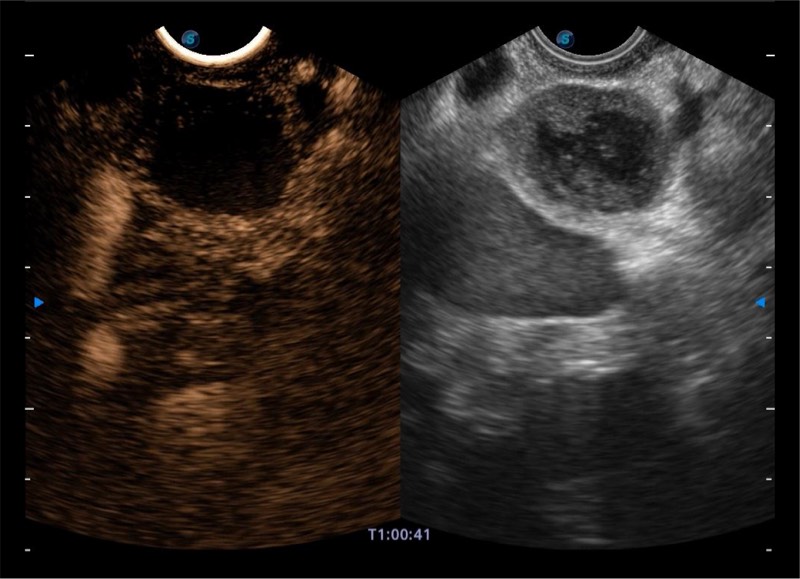

基于二十年的超声技术积累,1xBET提供了最新一代的独立超声主机,在提供高质量图像的同时满足多学科使用。具备常见多普勒技术并提供弹性成像、声学造影等高端影像技术。新一代传感器具有更强的抗干扰能力并减少图像伪影。